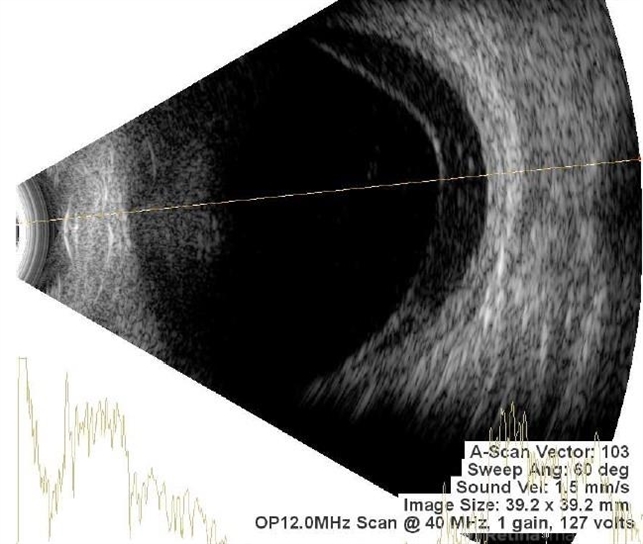

- B scan ultrasound, A-scan ultrasound, subhyaloid hemorrhage, subhyaloid blood, SUBHYALOID HEMORRHAGE

- Ultrasonography device

- Multiple dot echoes with mild to moderate spikes with free after movements suggestive of subhyaloid haemorrhage.